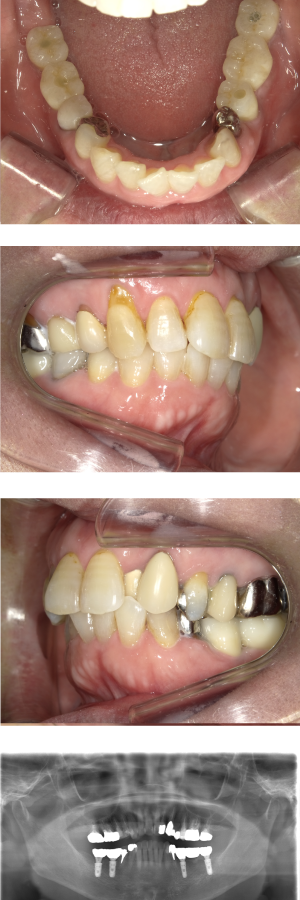

30代 女性 奥歯 インプラントGBR

| 年代・性別 | 30代・女性 |

| 治療回数 | 1回 ※術前治療・検査除く |

| 治療期間 | 5ヶ月 |

| 料金 | ¥60,000(税込) |

GBR(Guided Bone Regeneration:骨再生誘導法)とは、インプラント治療において、骨の厚みや高さが足りない場合に行う歯槽骨を再生する方法です。骨量不足の患者様でも、骨造成を行うことでインプラントの埋入に必要な骨の高さや厚みが得られます。 GBR(再生誘導法)は、骨が痩せて十分な骨量が確保できない患者様に、骨の再生によってインプラントの埋入を可能にする治療方法の一つです そのような骨が欠損した部分では、骨を作る「骨芽細胞」よりも、骨にならない「線維芽細胞」の方が増殖しやすいという特徴があります。そのためGBRでは、骨形成の妨げになる繊維芽細胞の侵入を防ぐため、骨を増やしたい部分を「メンブレン」という人工膜で覆い、その中に自家骨や人工の骨補填材を詰めて骨芽細胞の増殖を促します。 |

| 副作用 | 術後に腫れ・痛みが出る可能性がある。 |